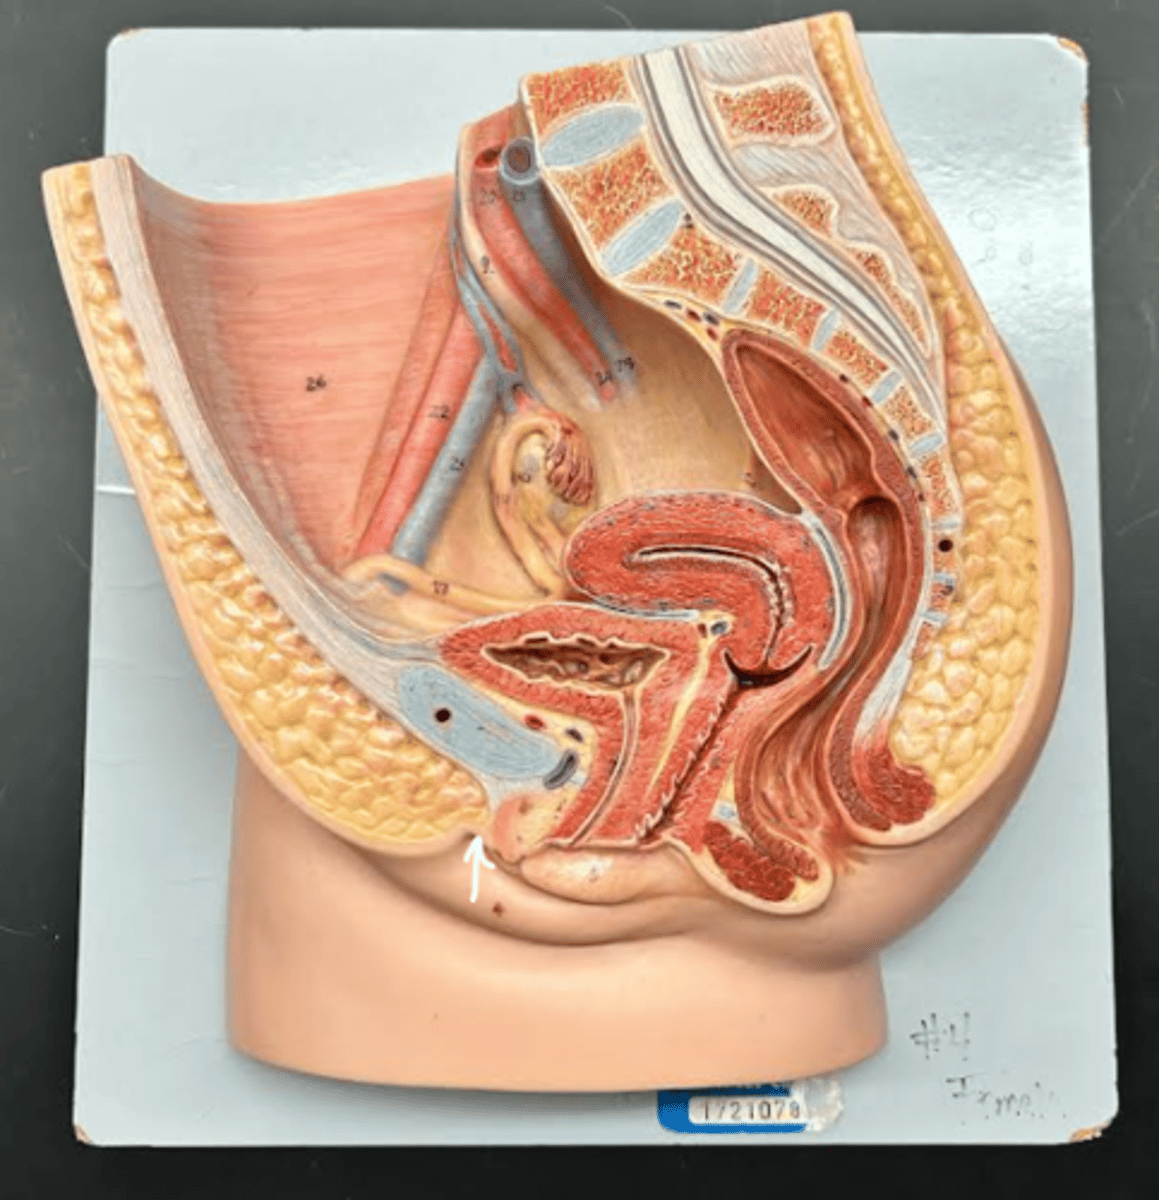

Chapter 29 Anat Phys: Female Reproductive System

Vagina

Vaginal orifice

Hymen

Vaginal fornix

Ovary

Fallopian tube

Fimbriae

Infundibulum

Ampulla

Isthmus

Uterus

Perimetrium

Myometrium

Endometrium

Fundus

Body of uterus

Cervix

Internal os

Cervical canal

External os

Labia majora

Labia minora

Prepuce

Vestibule

Clitoris

External urethral orifice